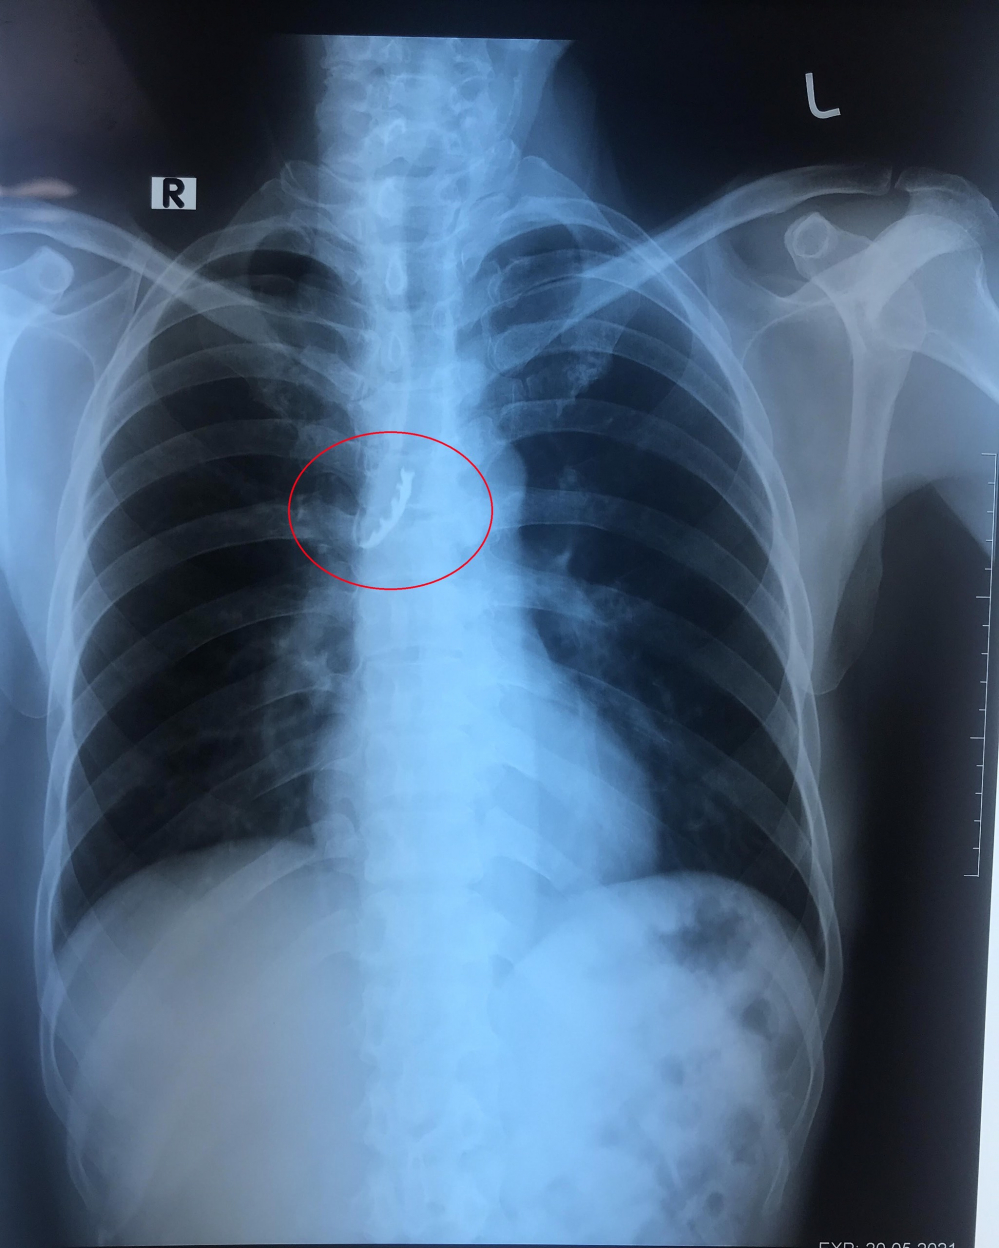

Theo các bác sĩ Bệnh viện Đa khoa Trung ương Cần Thơ cho biết. Họ đã nội soi can thiệp thành công. Tháo lắp 4 chiếc răng giả bị kẹt trong phế quản cho một bệnh nhân.

Trước đó, bệnh nhân nam tên C.V.P (sinh năm 1969, ngụ tại Cái Nước, Cà Mau) trong lúc ngủ quên tháo hàm răng giả, bệnh nhân có ho một lần trong đêm, sau khi ngủ dậy thấy 4 chiếc răng giả hàm trên bị mất kèm triệu chứng đau nhiều ở cổ nên đến bệnh viện địa phương khám, sau đó được chuyển đến BVĐKTW Cần Thơ vào ngày 20/5.

Sau khi nhập viện, các bác sĩ đã khám và thực hiện cận lâm sàng xác định vị trí dị vật, đồng thời tiến hành hội chẩn các chuyên khoa: Tai - Mũi - Họng, Nội hô hấp, Phẫu thuật – Gây mê hồi sức với chẩn đoán dị vật đường hô hấp.

Bệnh nhân có chỉ định nội soi phế quản ống mềm có gây tê để lấy dị vật, sau 30 phút nội soi đã can thiệp thành công dị vật là 4 chiếc răng giả ngay phế quản gốc phải của bệnh nhân. Hiện tại, tình trạng bệnh nhân khỏe, hết đau vùng cổ, phổi thông khí tốt, sinh tồn ổn định và ra viện trong ngày 22/5.